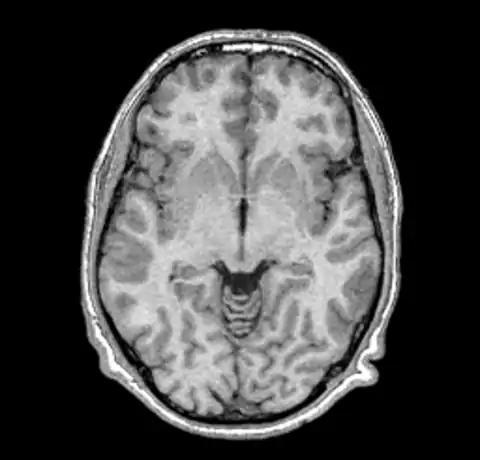

We can now take a look at the corrected file (out.mnc)

As it is very hard to pick the differences between the original and corrected version we can create a field image to visualise the differences.